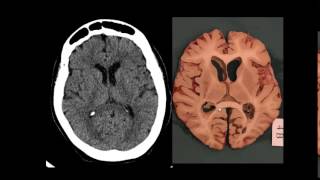

todo mais utilizado é o plano Nextel é o plano axial é como se cortasse a cabeça nesse sentido é a cabeça do paciente e E se a gente tivesse enxergando Oi manota são aqui aí você me disse tá aparecendo bem na tela tá para mim tá parecendo mas talvez fique um pouco escuro aí para na transmissão Então esse aqui é o olho tá sempre vou usar um desenho de um olho aqui para vocês terem uma noção do ponto de vista que a gente vai ter dois anos então como se estivesse olhando a cabeça do paciente

ocorre esse corte da cabeça paciente por baixo né de tal forma que a gente vai ter uma imagem com esse aspecto aqui é esse aqui é o plano axial é como se de cortar sua cabeça do paciente nesse sentido virasse o tampo da cabeça olhar super baixo Então vamos passei tivesse deitado na cama estivesse no pé aos pés do paciente e tal forma que sente estica o braço direito a gente vai pegar o pé por pé esquerdo do paciente né viu com a mão esquerda e vai pegar o pé direito do paciente então por isso

a gente está acostumado não sabe que se esticar a mão direita ela vai pegar no orelha isqueiro a pensou e vice-versa né então quando tem uma visão frontal eu acho que é mais incrível tive o pessoal não tem tanta dificuldade para entender a relação anatômica ali no exame de imagem então o pessoal que tá começando o Rogério falou que seria um pouco bem bem gordinho né que seria acompanha tal então a gente pega o exame deu demais pode assustar um pouco né então se o que parece o encéfalo é que a gente ver a superfície

dele vou começar pela tomei o bar tá foi falando de vários e depois de uma parte mais geral e depois aprofundando e detalhando a neuroanatomia do exame de Maio mas eu vou conversar com ela anatomia lugar porque eu acho que é relativamente é mais tranquilo e ao mesmo tempo é onde tem muitas dificuldades neles Olha o exame demais não sabe se a lesão tá logo frontal parietal se pelo altura do corte está no ar e tal atemporal né tem um pouco de dificuldade Então o que acontece com este óleo o exame de imagem né é